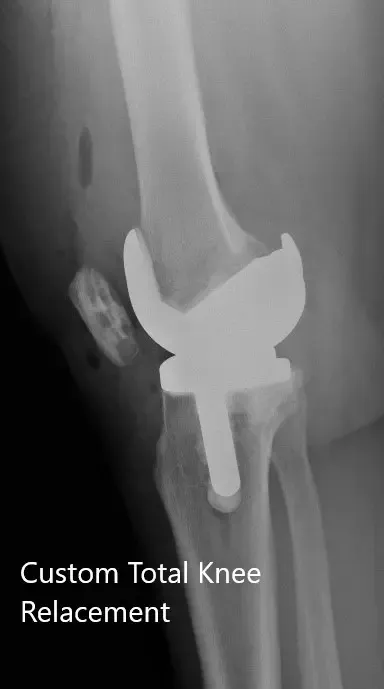

Los estudios de imagen revelaron osteoartritis tricompartmental severa de la rodilla derecha. Teniendo en cuenta el estilo de vida del paciente que limita el dolor de rodilla, se le recomendó un reemplazo total personalizado. Se discutieron riesgos, beneficios y alternativas con el paciente. Aceptó seguir adelante con la cirugía.

Como parte de la evaluación y planificación, se realizó una tomografía computarizada preoperatoria de las extremidades inferiores unas semanas antes de la cirugía. Se obtuvieron imágenes detalladas para una evaluación precisa de la anatomía y biomecánica del paciente. Se utilizaron datos completos para construir implantes e instrumentos personalizados y únicos para cada paciente.

IMPLANTES UTILIZADOS: Implante femoral personalizado con inserto de polietileno de 6 mm con una bandeja tibial personalizada y rótula de 32 mm.

Radiografía postoperatoria de la rodilla derecha que muestra visión AP y lateral.